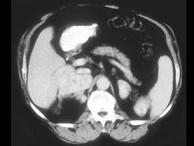

问题 女,32岁,阵发性高血压2年余,请结合所提供图像,作出诊断()

选项 A.左肾上腺腺瘤 B.左肾上腺腺癌 C.左肾上腺转移瘤 D.左肾上腺嗜铬细胞瘤 E.左肾上腺淋巴瘤

答案 D